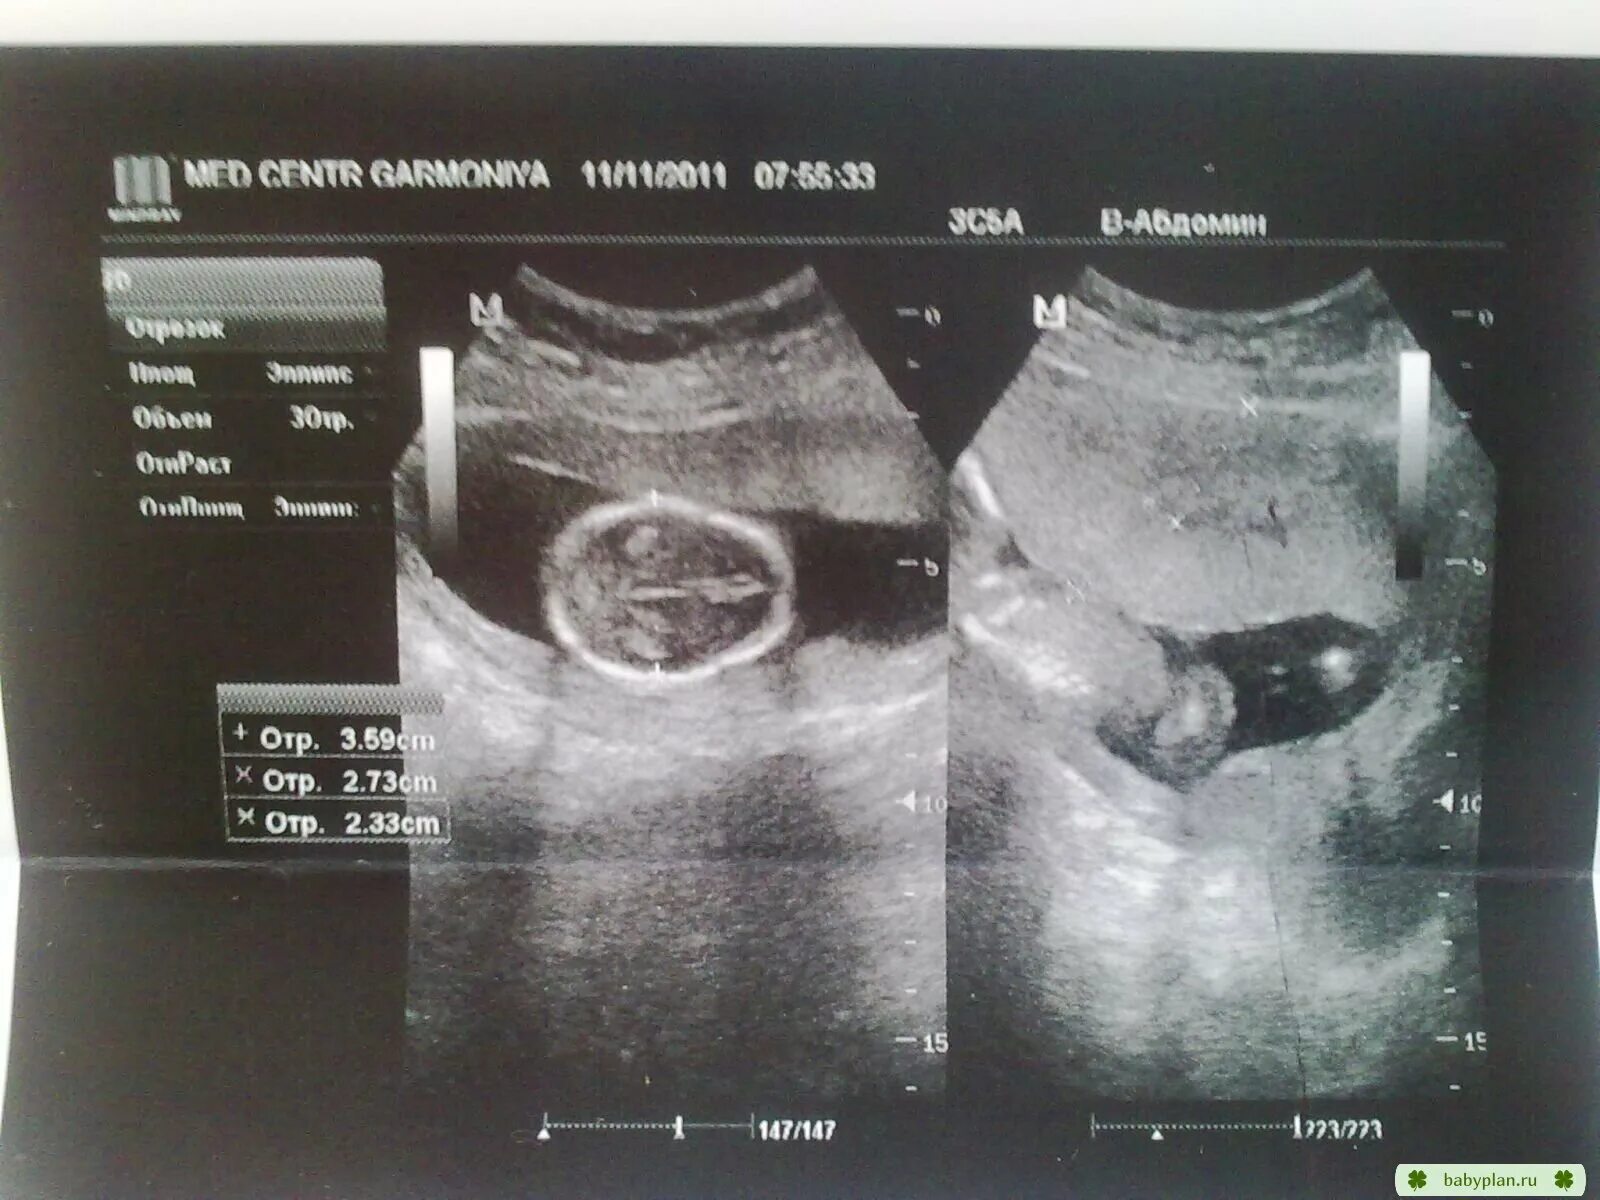

Как определить пол на 20 неделе